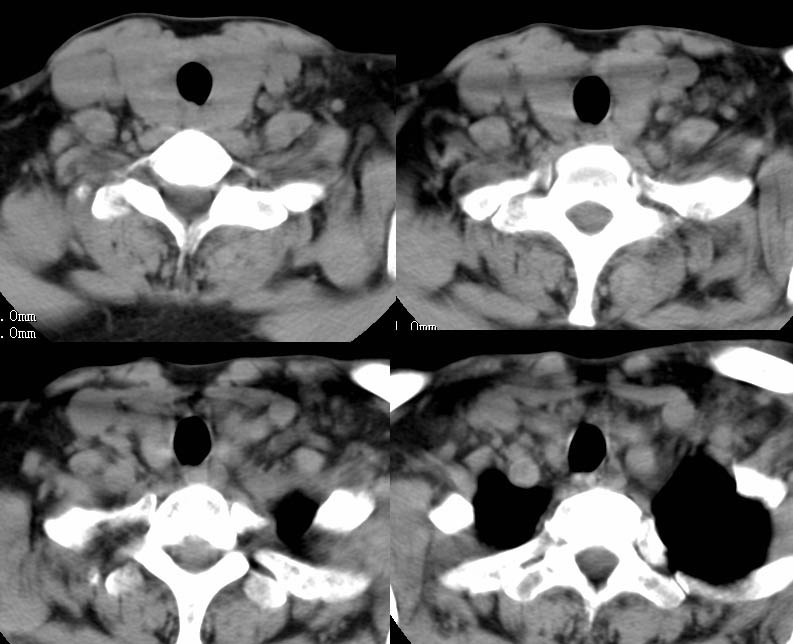

以下是引用zhangzhongshou在2007-4-23 12:41:00的发言:[br]甲状腺弥漫性肿大,密度减低,符合甲状腺炎ct表现,建议进一步检查